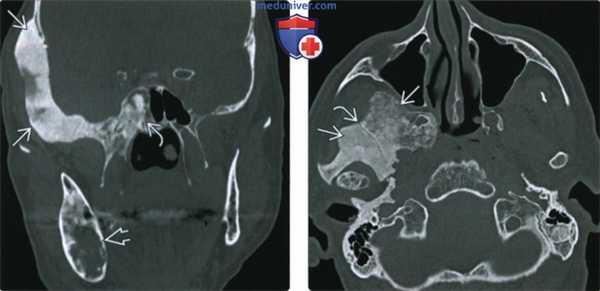

(Слева) При КТ в костном окне в корональной проекции определяется утолщенная чешуя височной кости неоднородной плотности. Также наблюдается утолщение клиновидной кости неоднородной плотности. В теле нижней челюсти определяется преимущественно кистозный (фиброзный) очаг поражения.

(Справа) При аксиальной КТ в костном окне у этого же пациента с полиоссальной фиброзной дисплазией определяются смешанные рентген прозрачные и склеротические изменения кости. Обратите внимание: шов резко разграничивает зоны различных изменений кости, что характерно для фиброзной дисплазии.

(Слева) При КТ в костном окне в аксиальной проекции определяется смешанная склеротическая и рентгенпрозрачная фиброзная дисплазия клиновидной кости и верхней челюсти. Обратите внимание на сужение левой крыловидно-верхнечелюстной щели. Дефект коркового слоя верхней челюсти - след выполненной ранее биопсии.

(Справа) При корональной КТ в костном окне у пациента с фиброзной дисплазией определяется обширное поражение тела клиновидной кости и крыловидных отростков. Отмечается также выраженное сужение левого видиевого канала, смещение и небольшое сужение левого круглого отверстия.